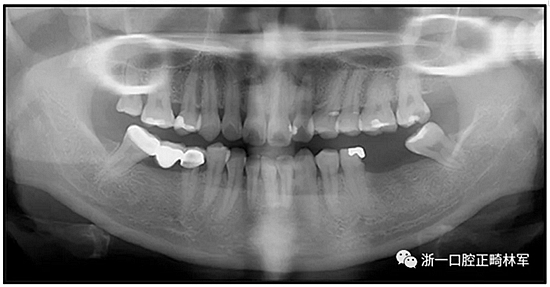

36歲;女性;尋求下頜左后方區(qū)域間隙管理的建議(圖1和圖2),通過治療獲得了良好的牙頜面效果(圖3和圖4)。她被診斷患有骨性I類和代償性牙性II類錯合畸形,并且上頜左側(cè)尖牙缺失(圖1和2)。大約七年前,由于不可修復(fù)的齲齒,拔除了下頜左側(cè)第一和第二磨牙(圖5)。37相鄰的第三磨牙向近中移動并傾斜入間隙,導致無牙頜間隙減小至約14 mm(圖2和圖5)。臨床和影像學評估顯示多發(fā)性齲損和在下頜右側(cè)567處有一不良的固定橋修復(fù)體(圖1和5)。此外,下頜左中切牙缺失,造成下頜中線向左側(cè)偏移約3 mm(圖1和圖2)?;颊咦栽V,她的右上第一前磨牙和左上尖牙在13歲時由其家庭牙醫(yī)拔除,因為它們被阻塞到頰側(cè)萌出(圖1)。上頜第二磨牙缺失(未知病因),并且相鄰的第三磨牙已經(jīng)轉(zhuǎn)移到第二磨牙間隙中。如補充材料所示,美國正畸學差異指數(shù)DI是28分。種植體部位(下頜左側(cè)和右側(cè)第一磨牙)由于復(fù)雜性得到額外4分(補充材料)。

總之,這種復(fù)合錯合畸形是一個很嚴重的問題,需要進行認真的多學科序列治療。治療后X光片(圖6)和重疊頭影測量圖(圖7)記錄了跨學科治療結(jié)果。

圖5. 治療前的側(cè)位片(上圖)和全景(下圖)的X光片